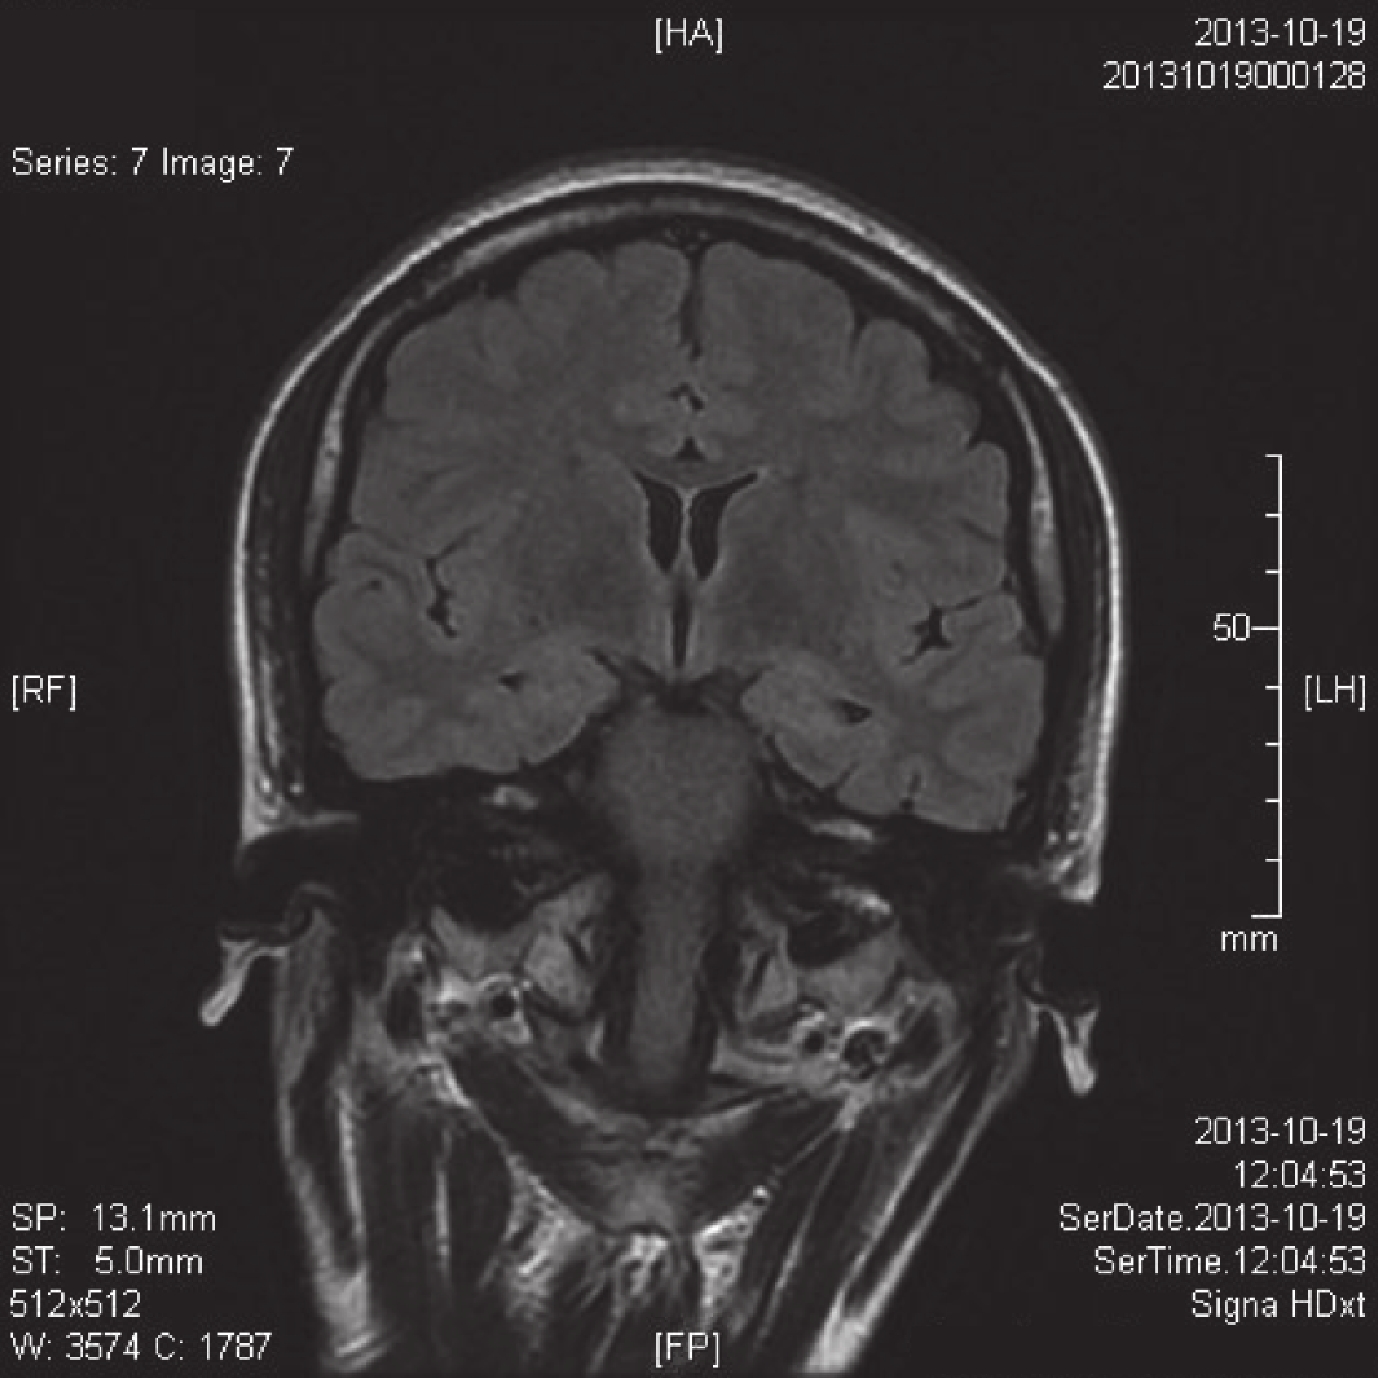

所有患者術前均行斷層掃描(CT)和核磁共振(MRI)檢查,CT 檢查均提示無明顯異常。MRI 檢查除了進行常規的 T1WI 和 T2WI 序列掃描外(圖 1),另外加行 FLAIR 序列掃描(圖 2)和雙側海馬 MRS 檢查(圖 3、4),均診斷為海馬硬化,其中左側海馬硬化 16 例,右側海馬硬化 26 例。海馬硬化 MRI 診斷標準包括:T1WI 顯示海馬體積縮小、側腦室顳角擴大、海馬區 T2WI 高信號以及 FLAIR 序列高信號,以及 MRS 檢查提示一側海馬 NAA/(Cr+Cho)<0.71 或者雙側海馬 NAA/(Cr+Cho) 差值>10%。